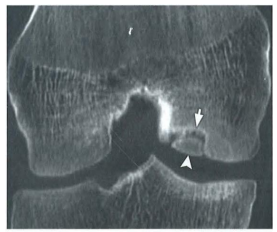

Tomografia do joelho abaixo

demonstra falha óssea na face lateral

do côndilo femoral medial (apontada

pelas setas). O diagnóstico

CORRETO é: